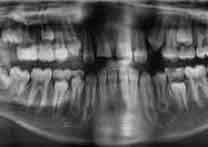

Before Treatment

OPG (Pre Treatment)

After Areatment

OPG (Post Treatment)

Case of full mouth rehabilitation All teeth extracted Upper single complete denture and lower Implant supported denture